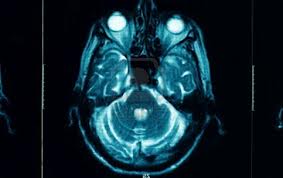

​大帥哥​腦開刀,竟變成無精症!   丈夫幾年前在長庚醫院,因為腦下垂體長腫瘤,開了腦部的刀,從此變成「低性腺刺激素低性腺素無精症」  ​,原本可以打造精針有精子的,可是他卻...